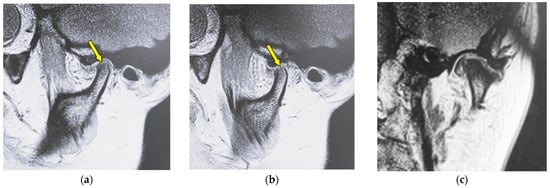

Figure 2 shows MR images of a 51-year-old woman with flattening (right TMJ). Sagittal oblique cross-section imaging (proton-density-weighted) shows anterior disc displacement in the mouth-closing position (Figure 2a) and in the mouth-opening position (Figure 2b).

Figure 2.

MR image (proton-density-weighted) of a 51-year-old woman (disc displacement without reduction, right disc): (a) sagittal oblique cross-section imaging in the mouth-closing position; (b) sagittal oblique cross-section imaging in the mouth-opening position; (c) coronal oblique cross-section imaging in the mouth-closing position. The arrow shows the part with flattening.